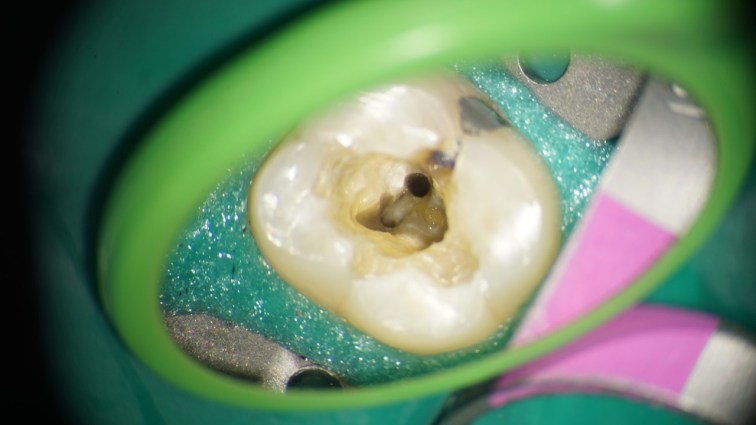

This is a “garden variety” endo. The best time to refer a case to an endodontist with a microscope is before the pulp has been touched. That way, the endodontist can control how much of tooth structure is removed to complete the endo. In this case, I had to chase all the cracks before restoring